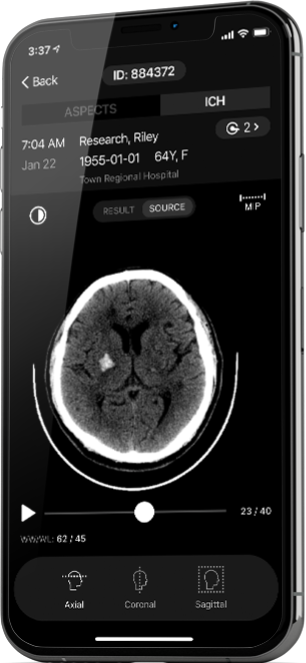

Rapid Mobile App

The Rapid Mobile App gives physicians the ability to receive anywhere, anytime notifications of new cases, preview Rapid results and source files, and enable workflow communications among stroke team members via their mobile devices.